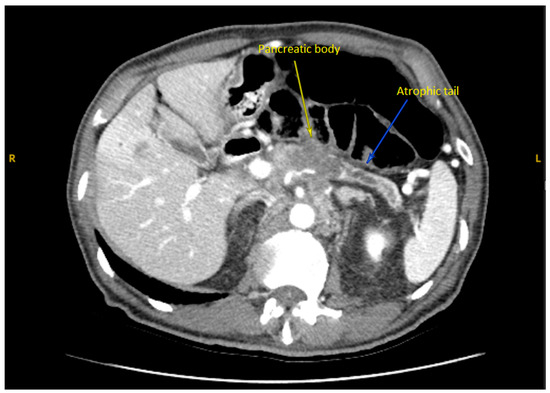

2. Case Presentation